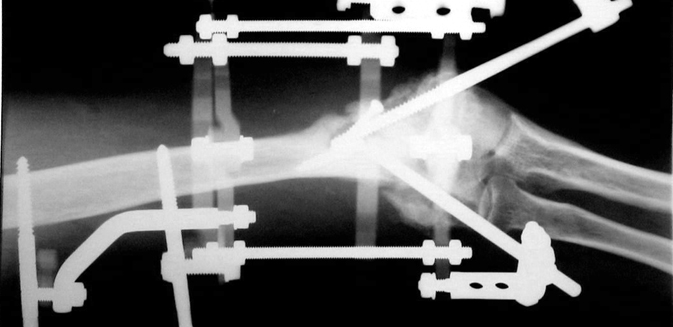

Vaka 1